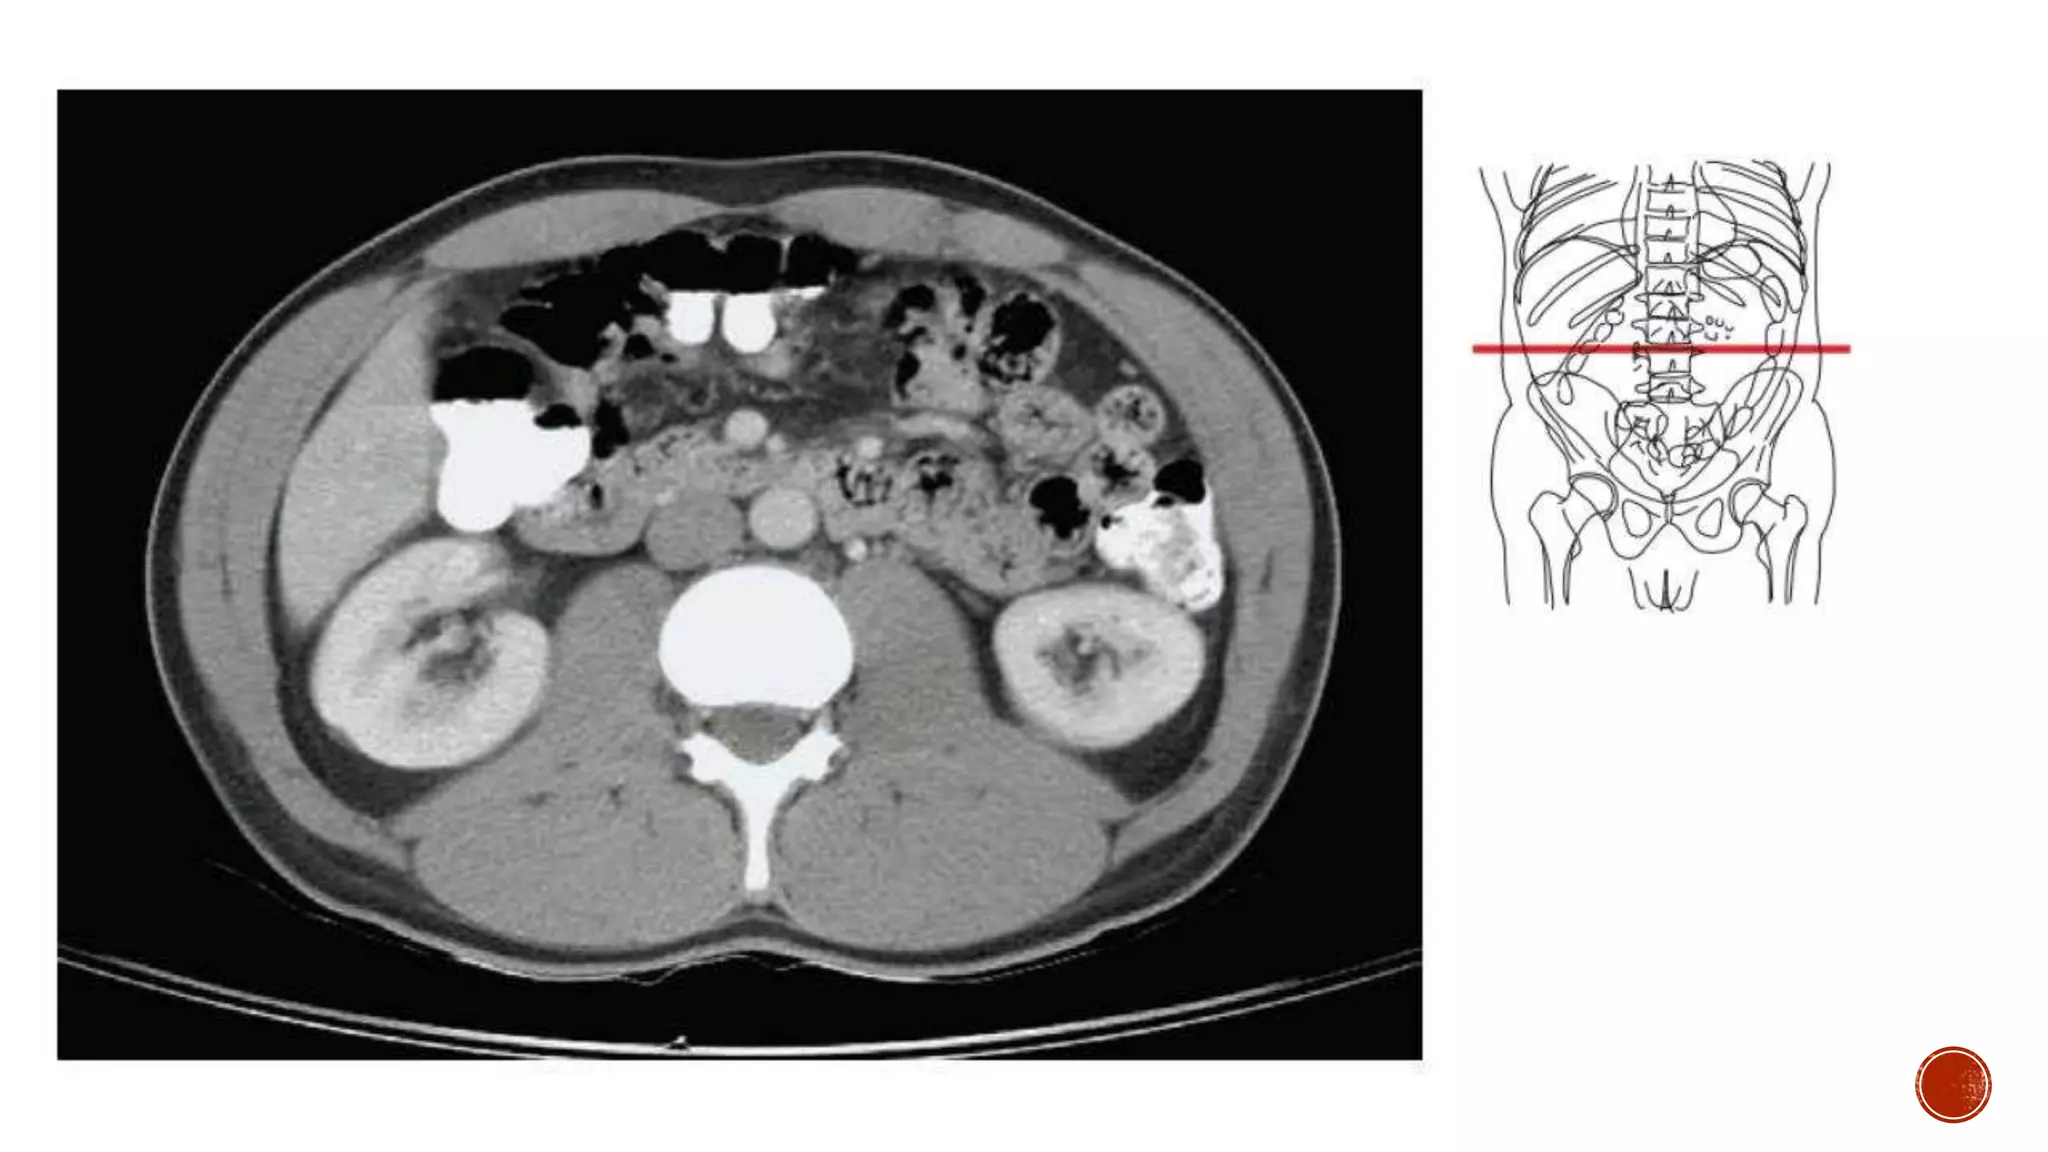

The document describes the anatomy of the abdomen and pelvis region of the human body. It lists over 40 structures and their locations, including major organs like the liver, kidneys, intestines, blood vessels and muscles of the abdominal wall and pelvis. The structures are grouped into sections focusing on different anatomical areas like the abdomen, retroperitoneum, pelvis and gluteal region.